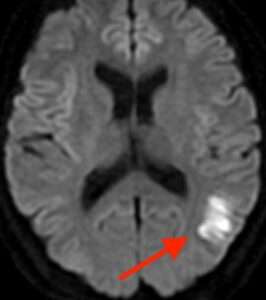

たとえば、脳の血管がつまる脳梗塞は、発症してすぐにはCTで写りません。MRIでも「拡散強調画像」という検査法を撮らなければ写らない時期があります。脳梗塞を疑い、MRIで拡散強調画像を撮って初めて、発症したばかりの脳梗塞を発見することができます。